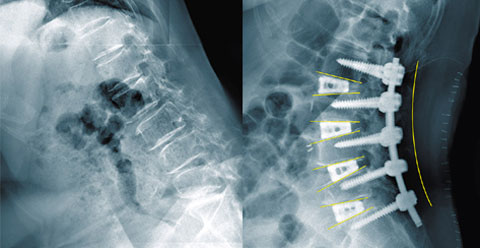

ÅðÇ༺ ¿äÃßÈĸ¸ÁõÀ¸·Î µîÀÌ ±ÁÀº ¸ð½À(¿ÞÂÊ)°ú ³ª»ç¸øÀ¸·Î °íÁ¤ÇÏ´Â ¼ö¼ú µÚÀÇ ¸ð½À. / ¿ì¸®µéº´¿ø Á¦°ø

¿ì¸®µéº´¿ø ¿¬±¸ÆÀÀÌ »õ·Î °³¹ßÇÑ ¼ö¼ú¹ýÀº ¹è ¾ÕÂÊÀ¸·Î ôÃß»À¿¡ Á¢±Ù, ź·ÂÀ» ÀÒ°í Á¦±â´ÉÀ» ¸øÇÏ´Â µð½ºÅ©¸¦ Á¦°ÅÇÑ µÚ Àΰøµð½ºÅ©¸¦ »ðÀÔÇÑ´Ù. ¶Ç Á¤»ó »óÅ¿¡¼­ ôÃß»À´Â ¹èÂÊ¿¡ ³ô¾Æ¾ß ÇÔ¿¡µµ ºÒ±¸, ¿©·¯ ¿øÀο¡ ÀÇÇØ ³»·Á ¾É¾Æ ³·¾ÆÁø ôÃß»À¿¡ ÀÎÁ¶»À¸¦ ³Ö¾î ³ôÀδÙ. ÀÌ·¸°Ô Çϸé ÁÖÀú¾ÉÀº ôÃß»À¿Í µð½ºÅ©°¡ ¿ø·¡ ³ôÀ̷Πȸº¹µÈ´Ù. ±× ´ÙÀ½ µîÂÊÀ¸·Î Á¢±ÙÇØ ôÃß»À¸¦ ¹Ù·ÎÀâÀº µÚ ³ª»ç¸øÀ¸·Î °íÁ¤½ÃÄÑÁØ´Ù.

Á¾Àü¿¡´Â ôÃß»À ¾ÕÂÊÀÌ ¹«³ÊÁ® ³ôÀ̰¡ ³·¾ÆÁø °ÍÀº ³öµÎ°í µî ÂÊ¿¡¼­¸¸ ôÃß»À¸¦ ³ª»ç¸øÀ¸·Î °íÁ¤Çϱ⠶§¹®¿¡ ¾ó¸¶ Áö³ªÁö ¾Ê¾Æ ³ª»ç¸øÀÌ ºüÁö´Â µî ¼ö¼ú ¼º°ø·üÀÌ ³·¾Ò´Ù.